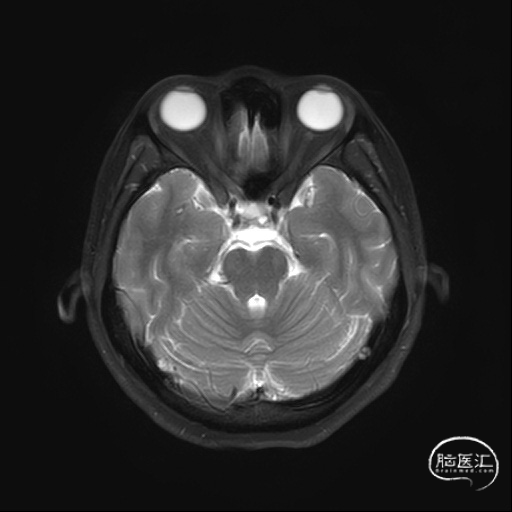

入院后完善多序列MR左侧颈内动脉C4段可见囊状突起、DWI未见新鲜梗死。

左侧颈内动脉造影提示:左侧颈内动脉C4段多发动脉瘤。大小分别为3.5mm*2.5mm、2.5mm*2.5mm,余各血管及其分支血管走形正常,动脉期、毛细血管期、静脉期均未见异常血管病变,脑循环时间正常。